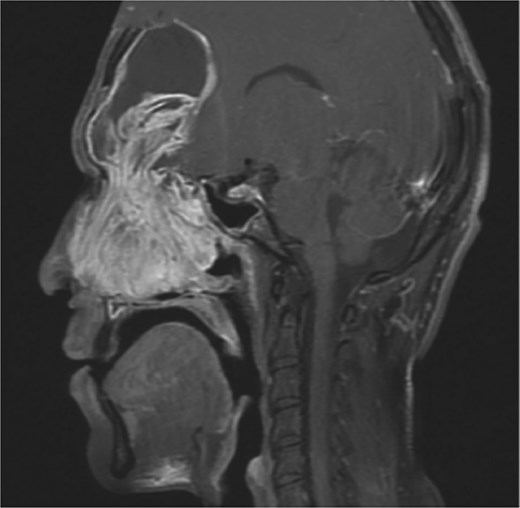

Preoperative non-contrast computed tomography (CT) scan of paranasal sinuses showed bilateral frontal sinus expansion, more pronounced on the left side with posterior wall dehiscence and soft tissue extension intracranially within the epidural space, measuring 5.3 × 4.1 cm. Preoperative MRI confirmed bilateral frontal sinus enlargement, with the left lesion measuring 4.7 × 6.5 × 6.7 cm and displacing the dura (Fig. 1).

MRI sagittal view of the brain and sinuses showing mucopyoceles causing significant bilateral frontal sinus enlargement.